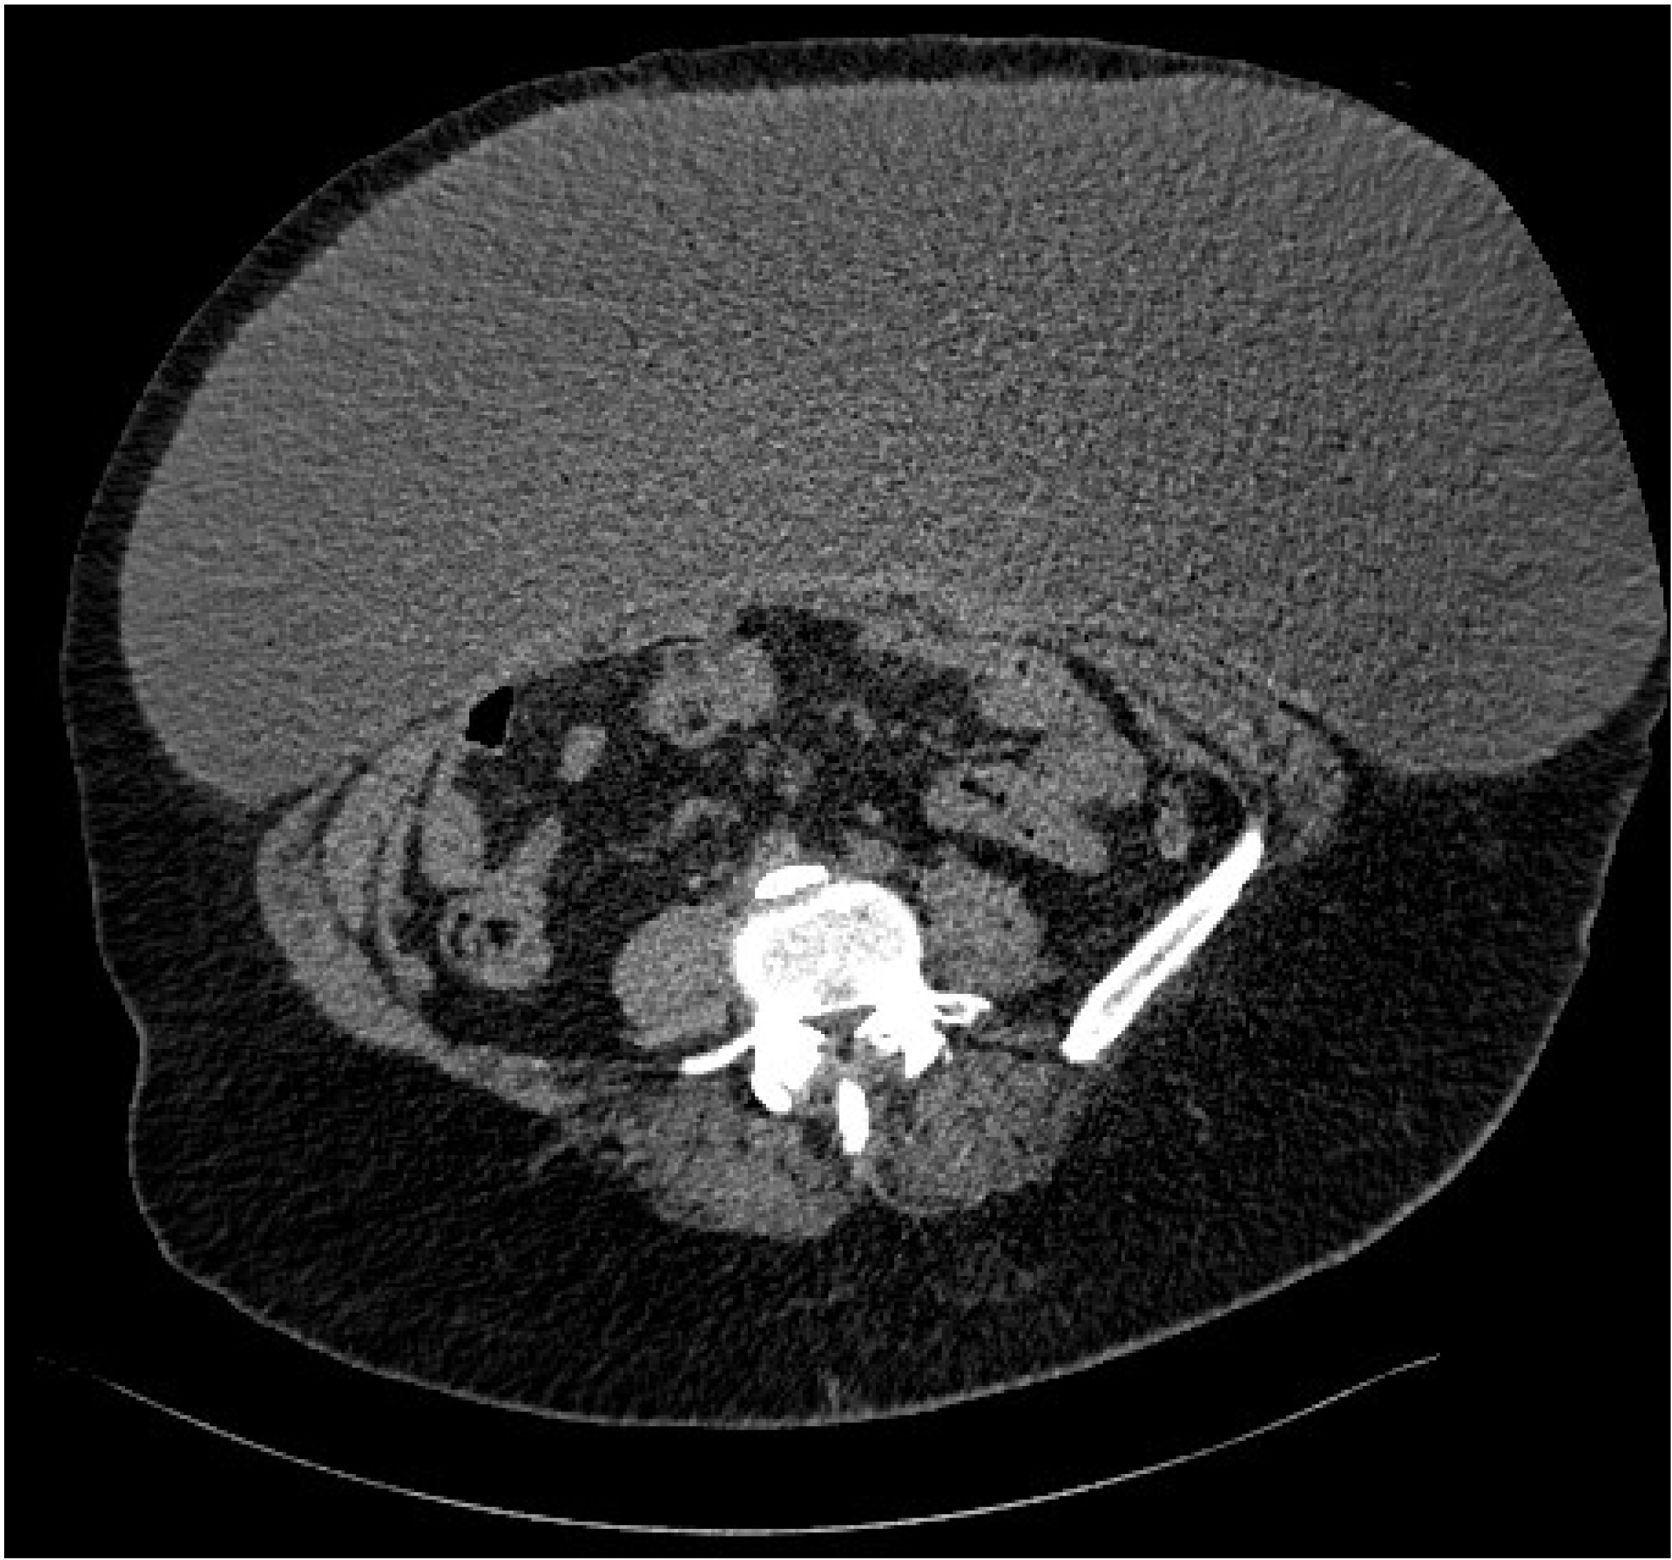

Giant seroma

Servicio de Cirugía General y del Aparato Digestivo, Sección de Cirugía Endocrina y Pared Abdominal, Hospital de Galdakao-Usansolo, Spain